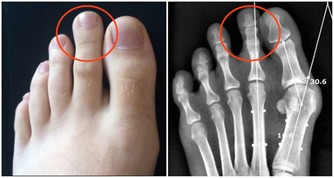

1.凌晨一點醒----肝經問題

肝臟經脈出現問題,則會在凌晨1點左右醒來。凌晨一點是氣血流經肝臟的時間段,如果肝火過旺,就會醒來。